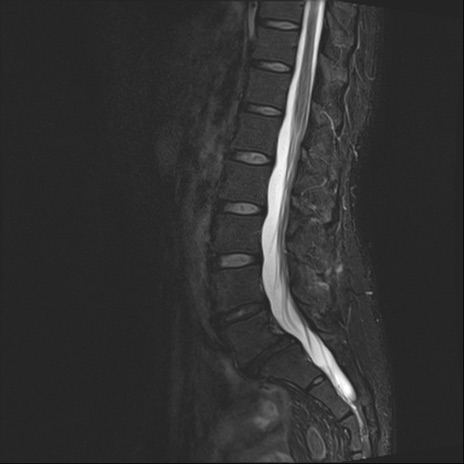

腰椎MRI

T2WI(矢状断像)